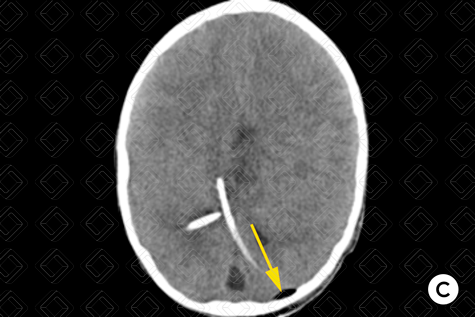

Descrição das imagens: Tomografia computadorizada do crânio: reconstruções na janela óssea (A e B) e parênquima encefálico (C). Exame realizado no paciente após troca do cateter de derivação ventricular, mostrando pequeno pneumoencéfalo (setas amarelas) adjacente à inserção do cateter. Observa-se a presença dos cateteres de derivação ventriculares (seta vermelha).